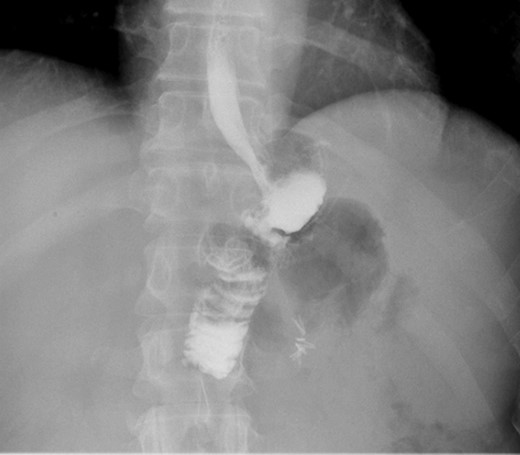

A 44-year-old female with BMI 25.5 with history of hepatic cirrhosis, upper GI bleed, GERD underwent LRYGB in March 2016, ventral hernia repair 2016. She presented to the clinic 1 year post 81 pounds weight lost since surgery with chronic colicky abdominal pain associated with nausea and vomiting. Vital signs were stable. On physical exam, she had tenderness in the right side of her abdomen and epigastric area. All the labs findings were unremarkable. Prior to this visit patient had an esophagogastroduodenoscopy (EGD) which was also negative. CT scan of abdomen shows hepato-splenomegaly with periappendiceal fat stranding and dilated appendix. Patient was taken to the operating room for diagnostic laparoscopy and appendectomy in April 2017 and was found to have candy cane syndrome. We resected excessive redundant (4 cm length) of the long blind jejunal loop of gastrojejunostomy anastomosis using Endo GIA Tri-Stapler device. Post-operative patient had upper GI which was normal (Figs 1 and 2). Post-operative course was uneventful. The patient was discharged to home on post-operative Day 2 and returned to clinic 2 weeks for follow up and tolerating diet and completely pain free.